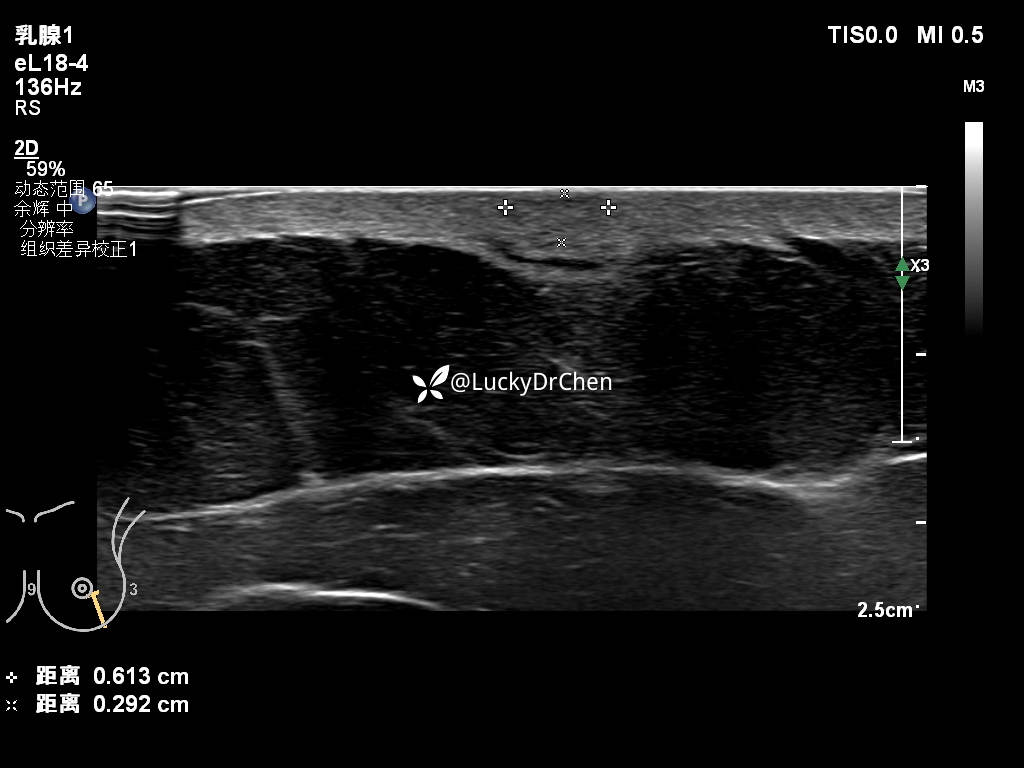

腋下肿大淋巴结